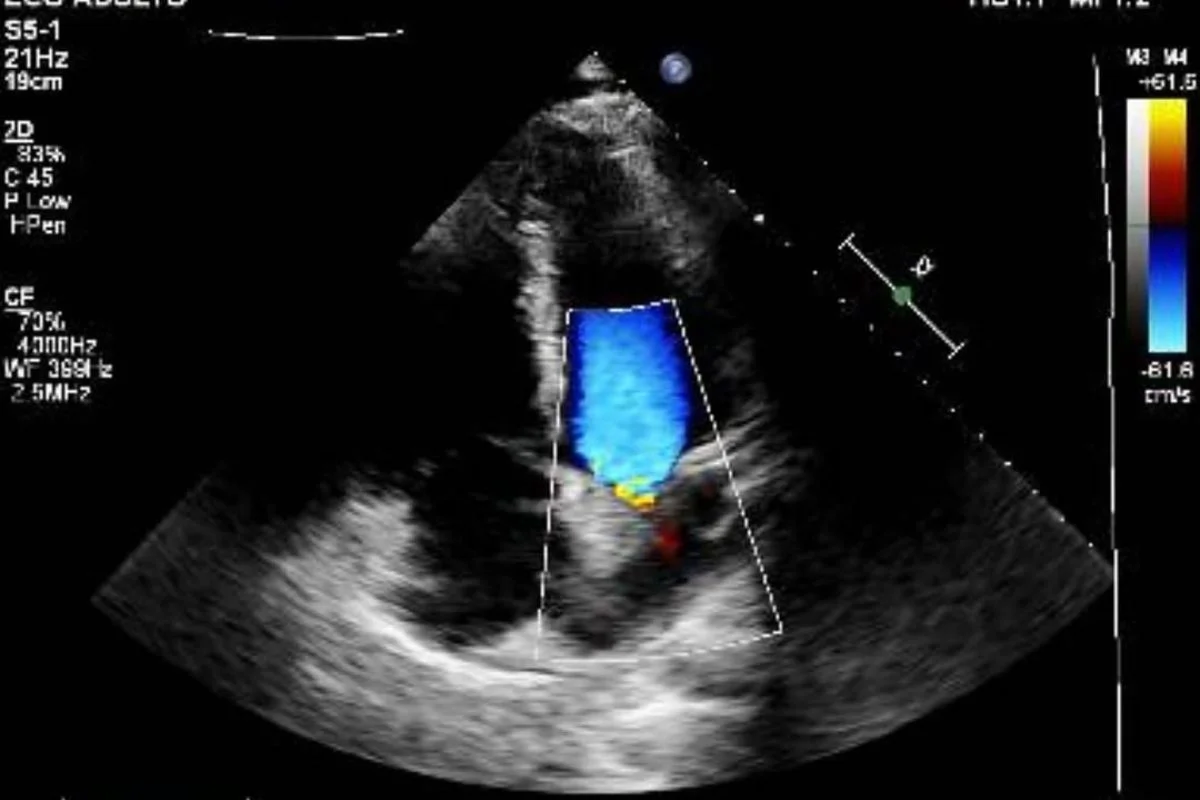

Vittor Fernando compartilha fotos da bala que atingiu seu coração